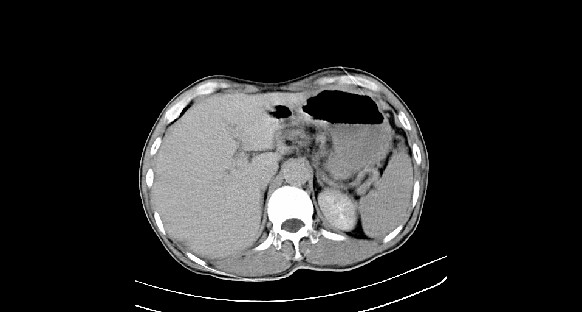

男性,70岁,体检b超发现左肾占位,请各位战友发表一下观点

左肾有两个病灶,且较大的病灶内可见点状钙化灶,增强扫描边缘也是呈渐进性强化,中央部分未见明显强化